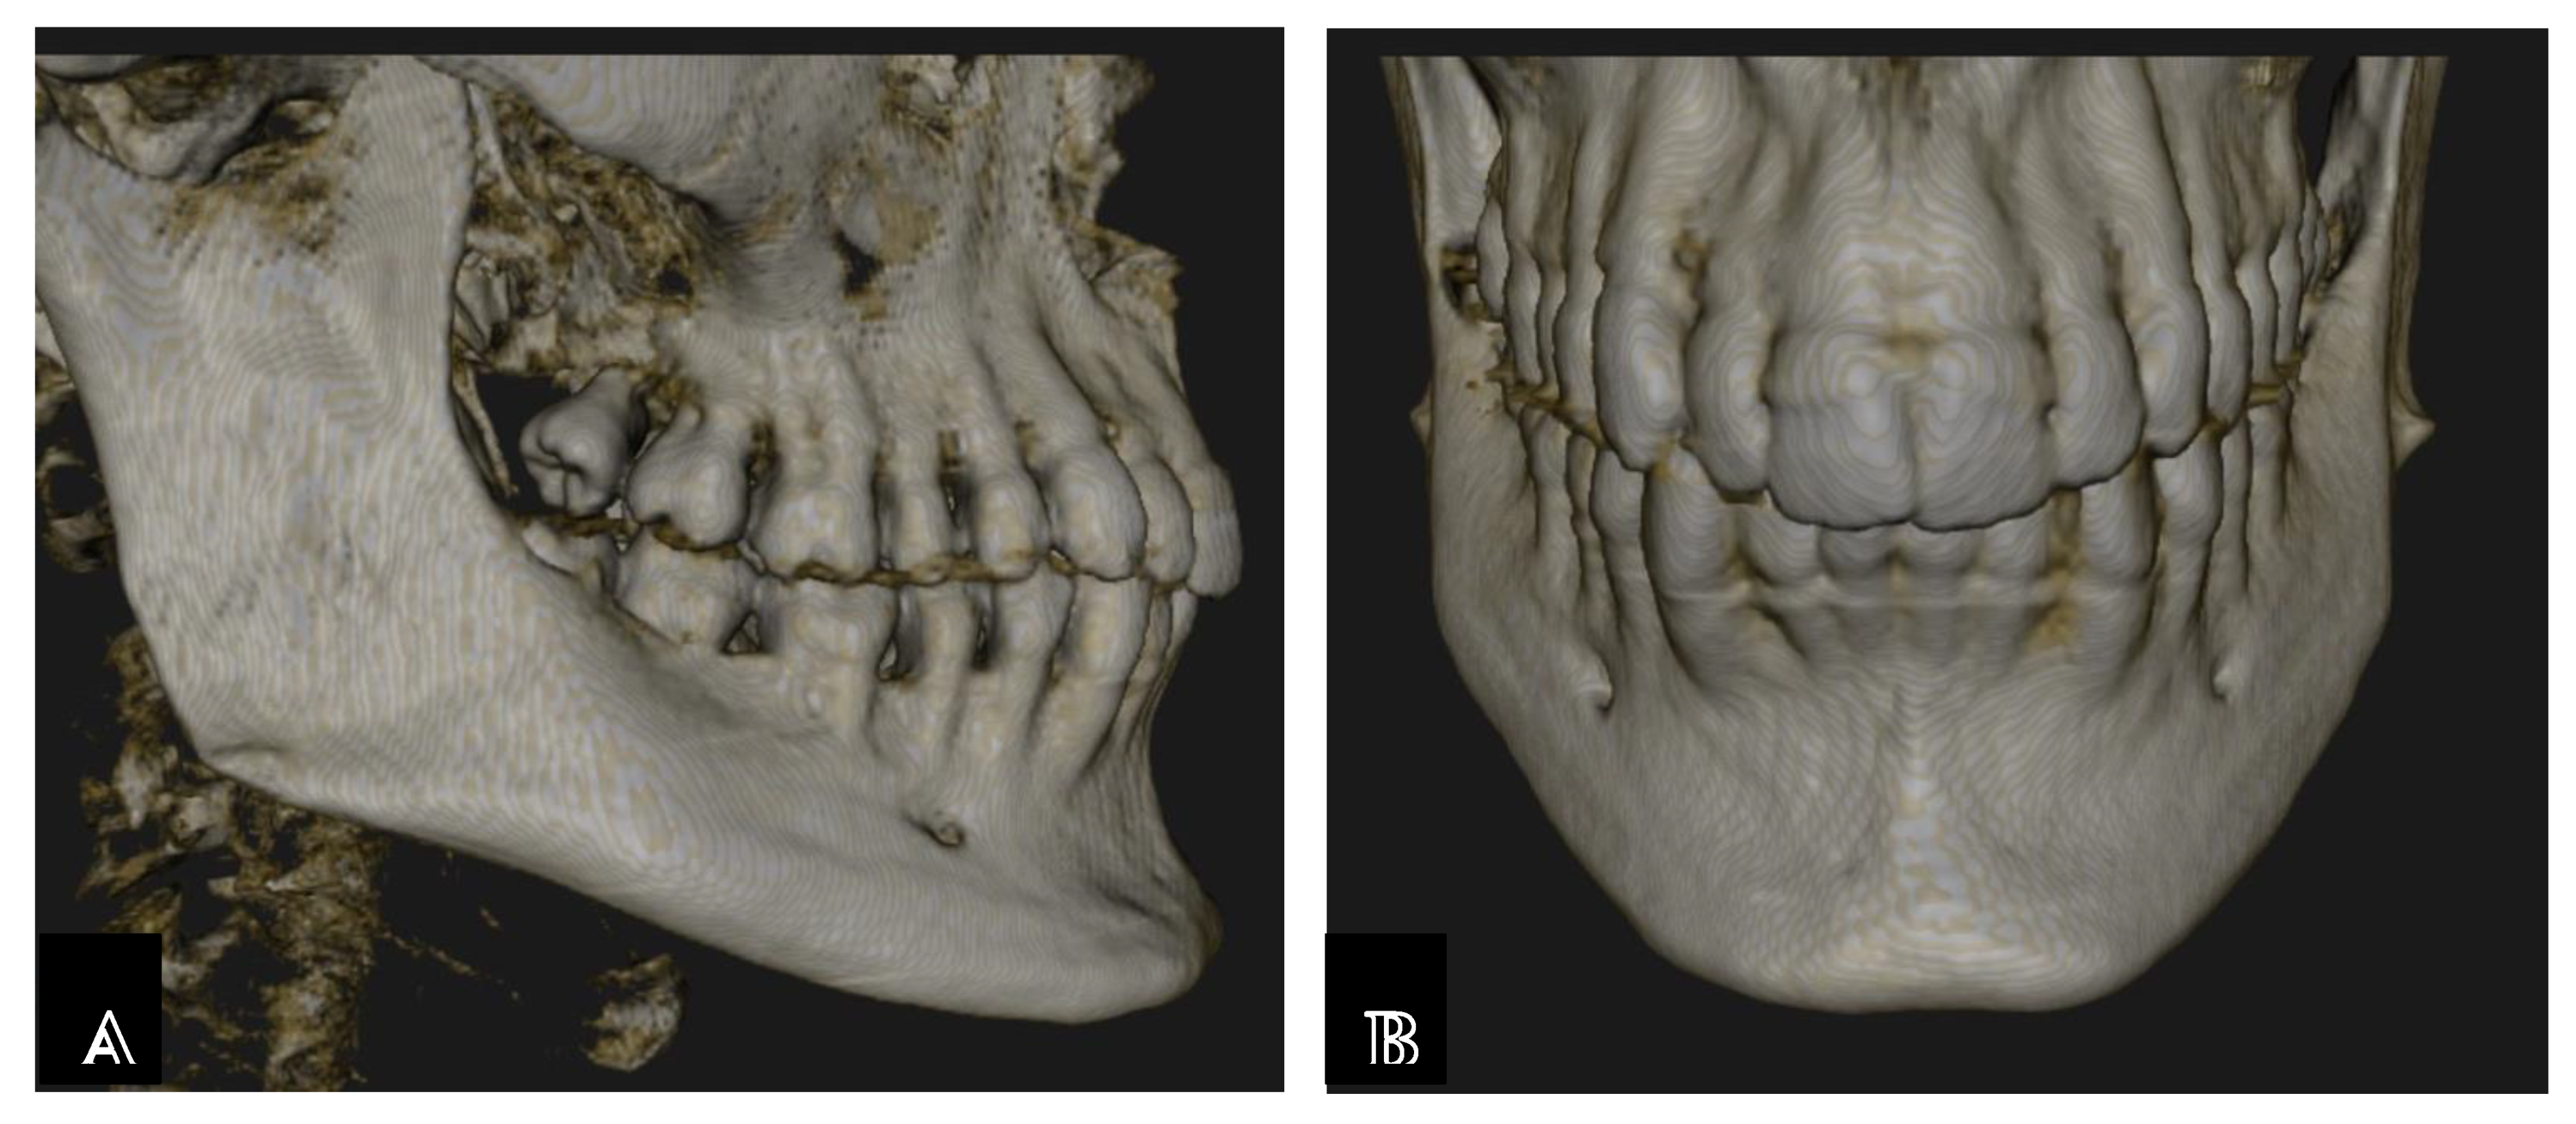

Assessment, Planning and Prevention in the Surgical Context

CBCT in the Post-Surgical Phase: Assessment of Bone Loss and Post-Operative Surgical Complications